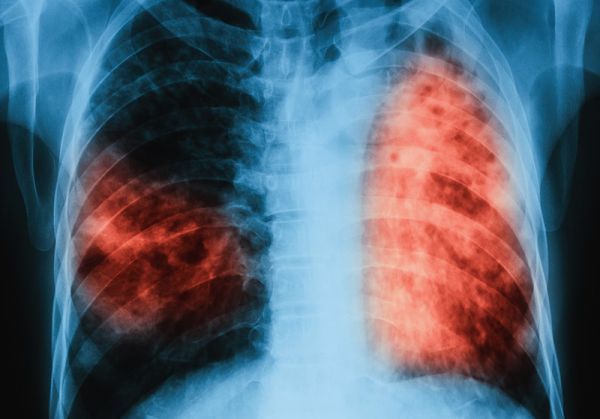

По време на проведени кампании през месеците март и юни 2019 г. общо анкетирани за туберкулоза са 5 057 лица, а на 3 293 лица в риск от туберкулоза са извършени медицински прегледи и допълнителни изследвания. Открити са 53 лица с туберкулоза и 144 лица с латентна туберкулозна инфекция, при които е започнато лечение.

Инициативата се провежда от 2009 г. и е допринесла за по-добра разкриваемост на случаите на туберкулоза и латентна туберкулозна инфекция, за ефективна превенция на туберкулозата в страната и за подобряване на достъпа до здравни грижи. По време на проведените за периода 2009 г. – 2018 г. „Седмици на отворени врати” анкетирани за туберкулоза са 119 787 лица, открити и насочени за лечение са 1 295 лица с туберкулоза, открити с латентна туберкулозна инфекция и обхванати с химиопрофилактика са 4 495 души.

По време на „Седмицата на отворените врати“ на всеки желаещ се предлага скрининг за риска от туберкулоза чрез анкета и консултации. На лицата, които са в риск, се провеждат допълнителни прегледи и изследвания. При откриването на случаи на туберкулоза своевременно се предприемат мерки за хоспитализация и лечение, в резултат на което се прекъсва веригата за предаване на инфекцията.